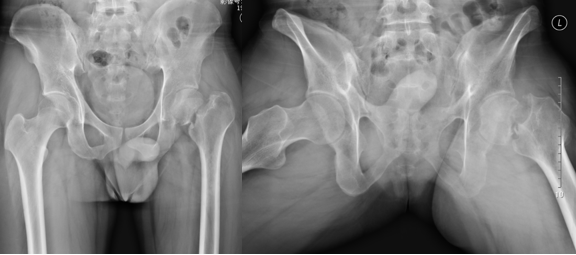

患者于5月前不慎从木梯上跌下,左髋部着地,左髋部稍有疼痛,未予重视,后反复外敷中药药膏,近10天患者走路较多,觉左髋部疼痛加重,且行走困难,于25/12至外院就诊,查双髋CT示:左侧股骨颈骨折;查双股骨头MRI:左髋关节股骨颈头下陈旧性骨折并左股骨头坏死(Ⅱ°),左髋关节滑膜囊少量积液。今为进一步治疗来我院就诊,门诊以"股骨头坏死"收入院。

辅助检查:双髋正侧位X片:左股骨颈陈旧性骨折。